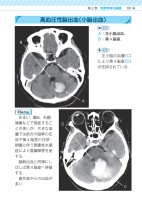

高血圧性脳出血(小脳出血) CTA:左小脳出血.B:第4脳室. CT 左小脳の血腫(C)により第4脳室(D)が圧排されている. めまい,嘔吐,失調,頭痛などで発症することが多いが,大きな血腫では前方の脳幹の圧迫や第4脳室の圧排・閉塞に伴う閉塞性水頭症により意識障害を呈する. 脳幹出血と同様にしばしば第4脳室へ穿破する. 歯状核からの出血が多い.MemoABCD第2章 疾患特有の画像101